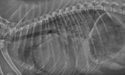

Right lateral thoracic radiograph of a small dog in ACVIM Stage C, heart failure.

Image courtesy of Rebecca L. Stepien, DVM, MS, DACVIM (Cardiology), University of Wisconsin, USA